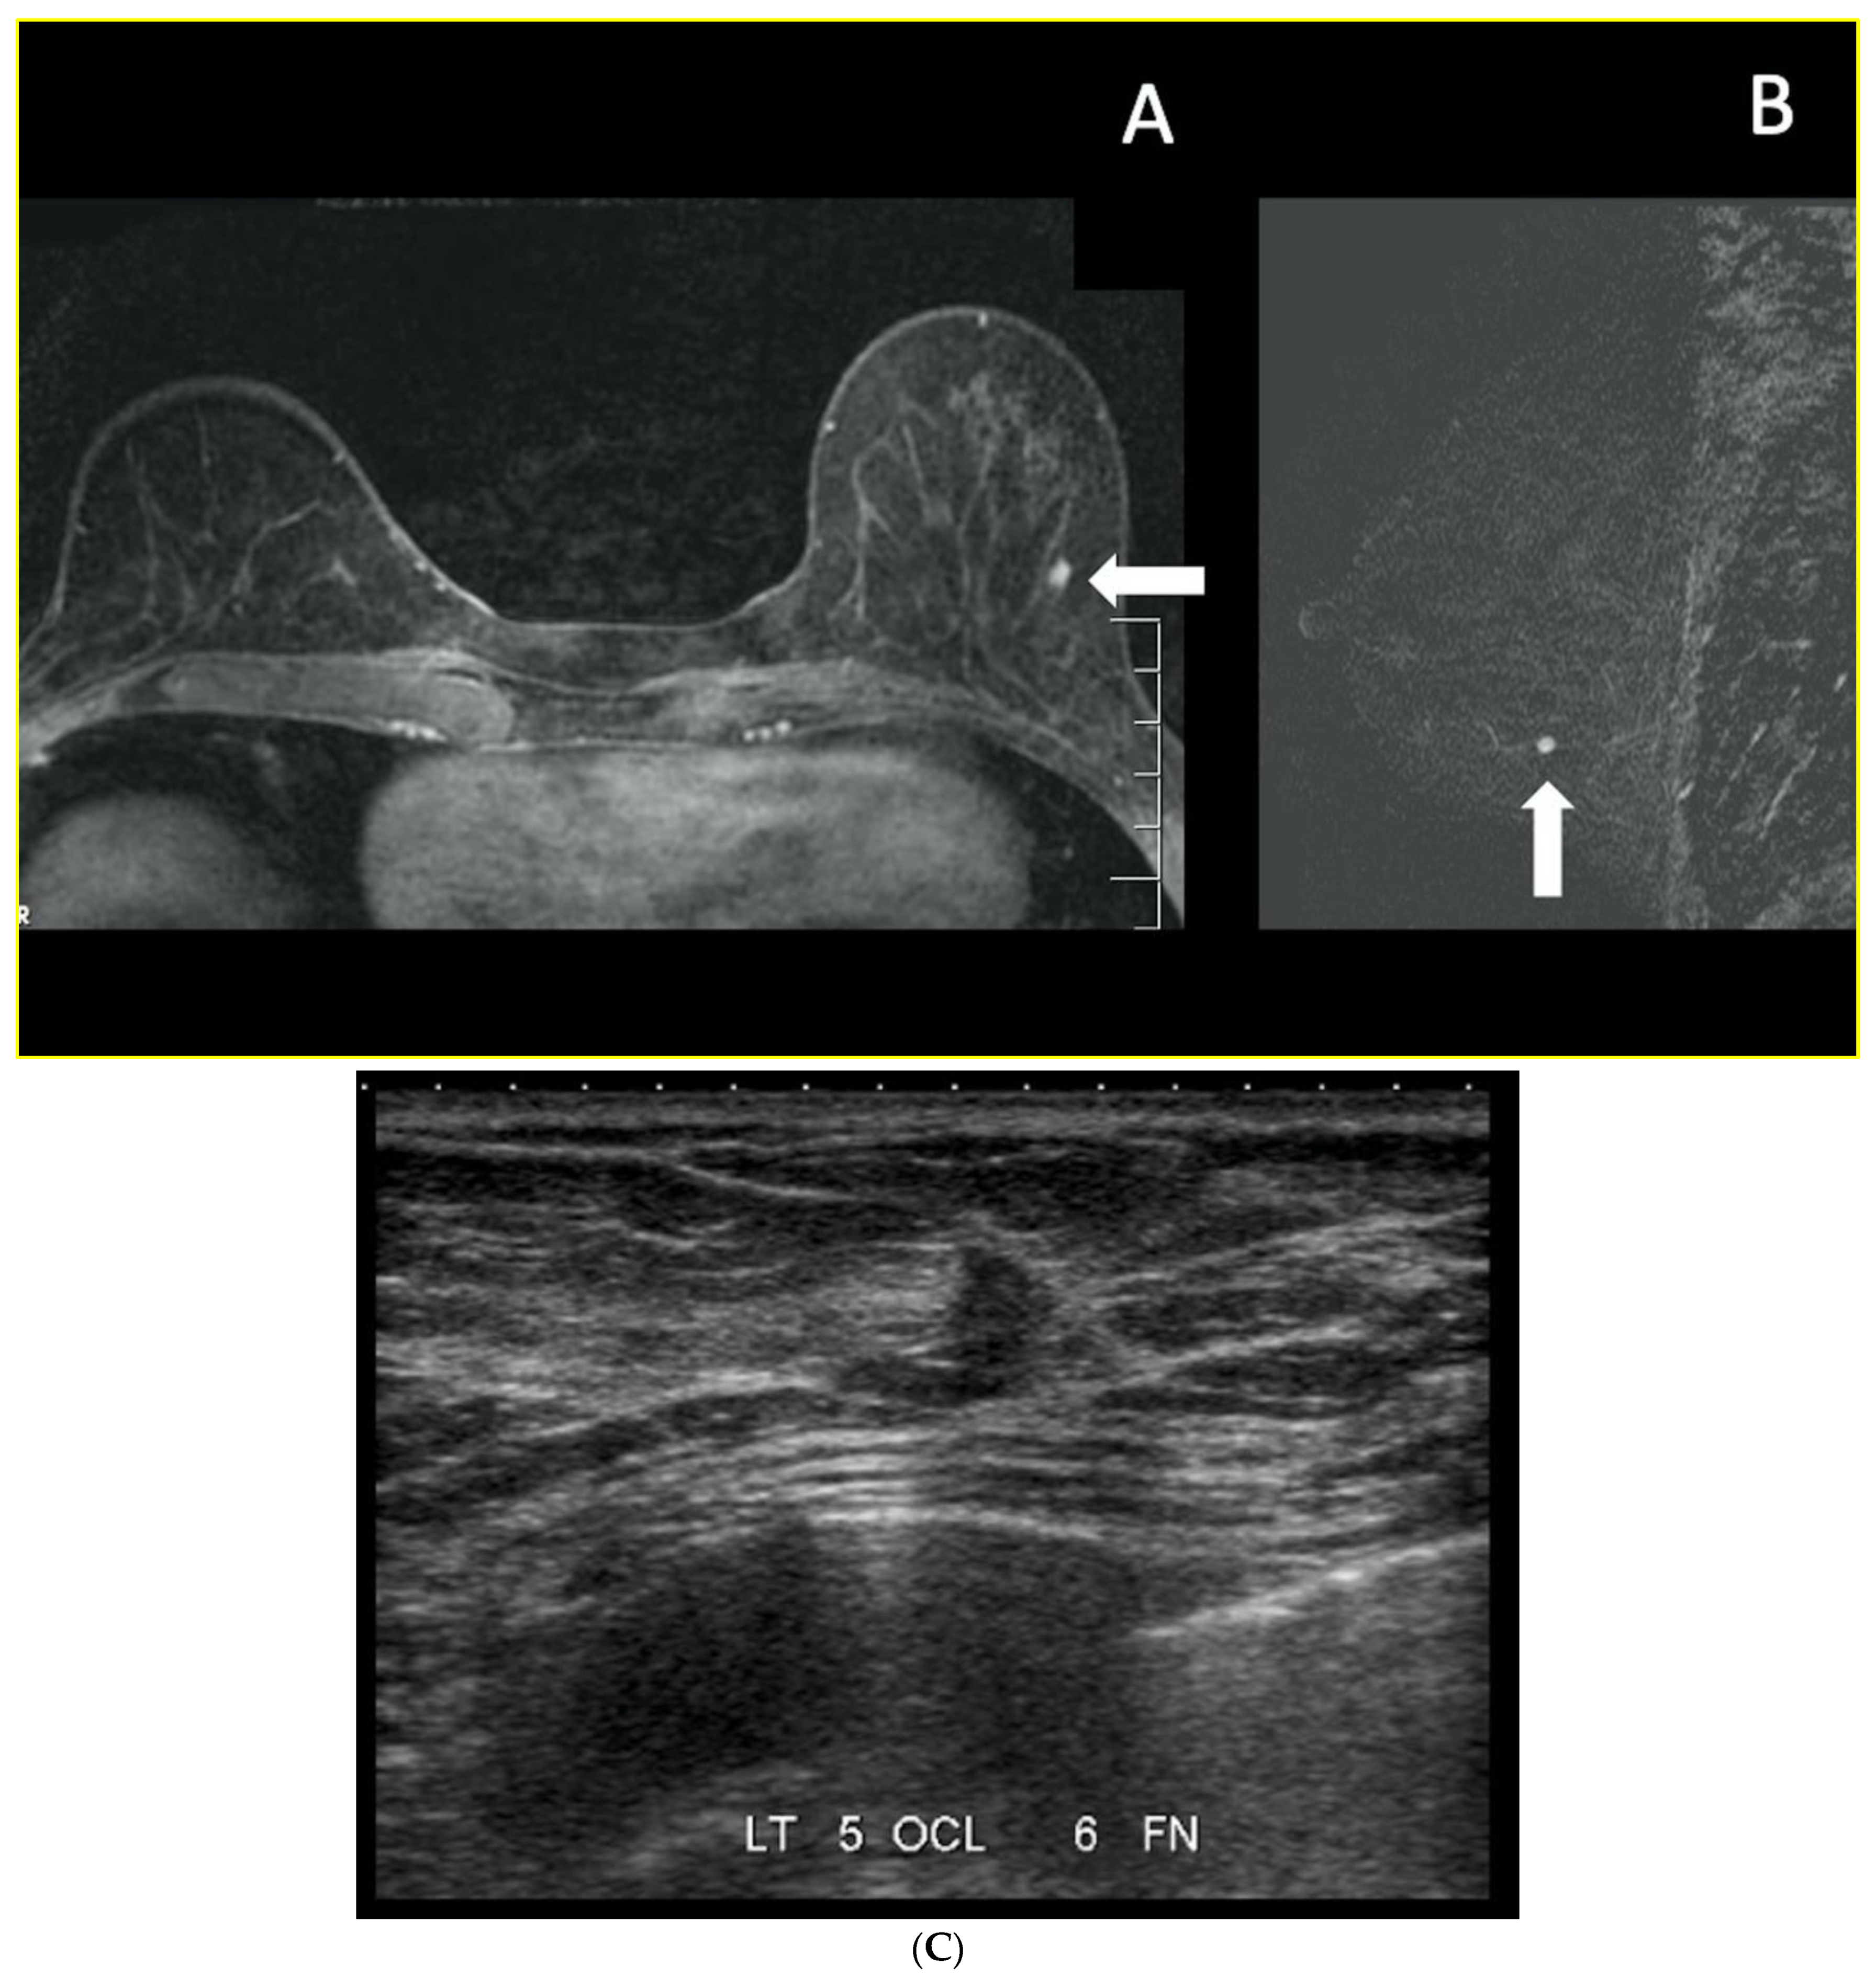

7. Magnetic Resonance Imaging (MRI)